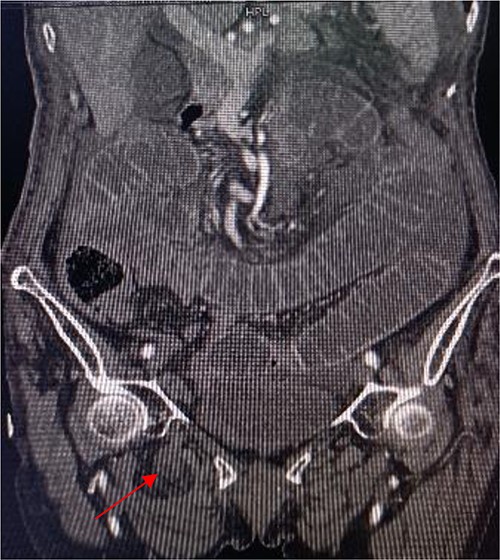

An 86-year-old female complained of constipation with abdominal pain, nausea, and vomiting for ˃2 weeks. The patient had defecated once, after conservative treatment with an enema in a local hospital, with less abdominal pain and no nausea or vomiting; hence, she was admitted to our hospital for further diagnosis and treatment. The patient’s body temperature was 36.8°C, pulse rate was 87 beats/min, respiration rate was 18 breaths/min, and blood pressure was 125/76 mmHg. The patient was conscious and had a thin appearance, and physical examination indicated that the abdomen was soft, and without tenderness and rebound pain. Routine blood examination showed that hemoglobin was 87 g/L and hematocrit was 28.3%. Abdominal computed tomography revealed the right lower abdominal small intestine protruding into the femoral triangle through the obturator; the upstream intestine was distended and expanded, and multiple fluid levels were observed in the intestinal lumen. Multiple lymph nodes were noticed in the abdomen and retroperitoneum; the large ones had a diameter of ~1 cm. Uneven thickening and enhancement of the local ascending colon were noted.

Computed tomography axis map showing the small intestine entering the femoral triangle (red arrow).

Sagittal view shows a right obturator hernia (indicated by red arrow).

Coronal view shows right obturator hernia entering the intestinal canal (indicated by red arrow).